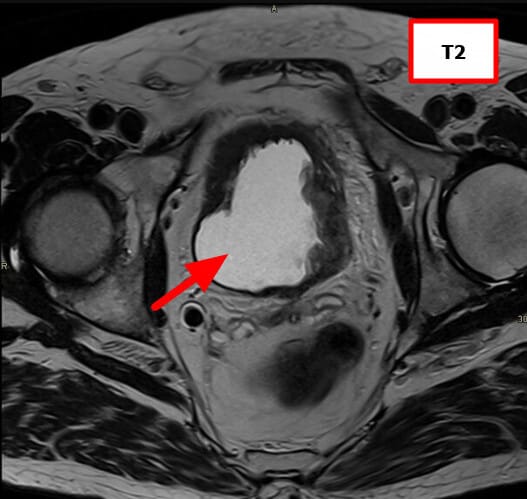

방광암 (Bladder Cancer)

[임상양상]

– 가장 특징적인 증상은 무통성 육안적 혈뇨입니다.

– 빈뇨, 배뇨통, 잔뇨감 같은 자극 증상이 동반될 수 있습니다.

– 진행 시 골반통, 수신증(요관 폐쇄), 체중 감소 등 전신 증상이 나타날 수 있습니다.

[진단]

– 소변검사: 혈뇨 확인.

– 소변세포검사: 암세포 확인 가능.

– 방광경검사(Cystoscopy): 진단의 gold standard, 직접 종양 확인 및 조직생검 가능.

– 영상검사(CT urography, MRI): 종양의 범위 및 전이 평가.

– 병리검사: 요로상피암(urothelial carcinoma), 편평상피암, 선암 등 조직학적 아형 구분.

MRI (Magnetic Resonance Imaging)

연부조직 대비가 뛰어나 방광 침윤 깊이를 정밀하게 파악